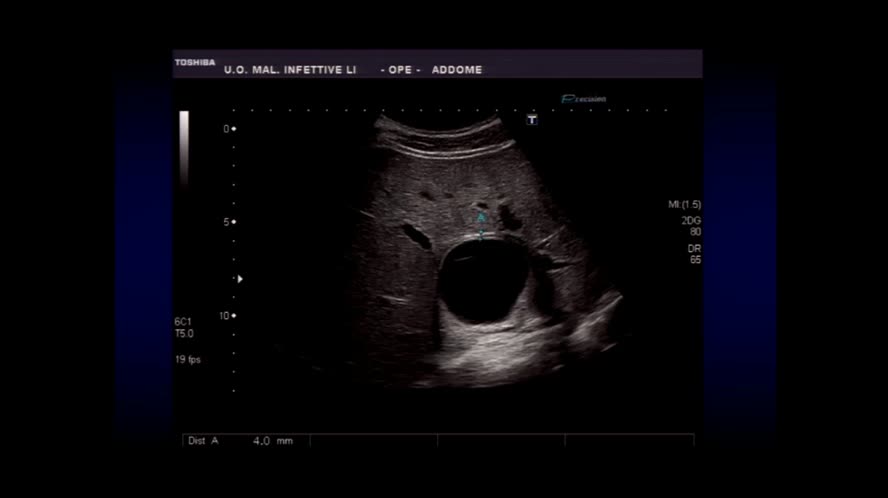

Infezioni renali e del tratto genito-urinario maschile

Congresso

: Ecografia Clinica nelle Malattie Infettive

Autori

: A. Granata |

Data

: 21 marzo, 2016 |

Lingua

: ITA |